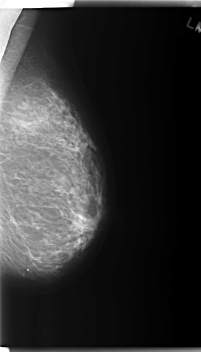

C_0183_1.LEFT_CC

LEFT_CC LINES 6016 PIXELS_PER_LINE 3368 BITS_PER_PIXEL 12 RESOLUTION 50 NON_OVERLAY